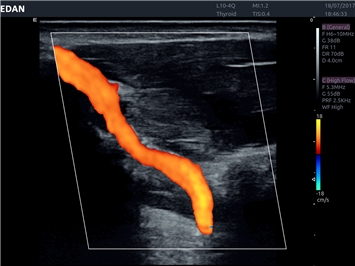

EDAN Acclarix LX4 представляет собой инновационную ультразвуковую систему, построенную на усовершенствованной платформе Acclarix. Сочетание высокого качества визуализации с интеллектуальным рабочим процессом делает эту систему оптимальным выбором для клиник, ценящих эффективность и экономичность.

• Сосудистой диагностики

Трехмерная реконструкция ЦДК:

Да

Направленный энергетический допплер:

Энергетический допплер:

Цветовой допплер: